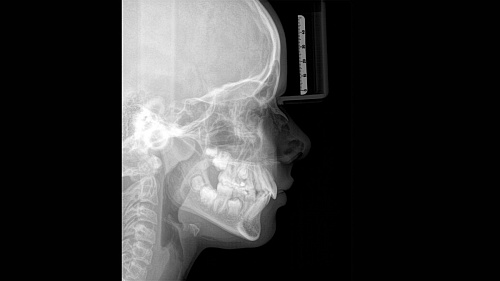

При помощи такого оборудования специалист сможет успешно решить широкий спектр диагностических и лечебных задач. Качественное изображение, достоверность при разноуровневой резкости (технология Sharp Layer), гибкий объём, 30 доступных вариантов цвета. Цефалометрическая визуализация позволяет получать боковые или симметричные снимки, а также определить положение при смещении зуба. Работая при разрешении до 80 мкм в режиме низкой дозы и HD, вы получаете качественные изображения выбранного формата, заботясь о комфорте и безопасности пациента.

Чтобы предприятие функционировало «как часы», не последнюю роль играют такие факторы, как экономичность и продуктивность. Среди достоинств ORTHOPHOS SL 3D – возможность зафиксировать голову в трёх точках, что повышает комфортность не только работы врача, но и пациента; световые центраторы, накусочная окклюзионная пластина по запатентованной технологии; сенсорная панель Easypad; специальное ПО SIDEXIS 4.

ORTHOPHOS SL 2D использует цветовые сигналы и специальные символы для изображения правильной схемы положения головы пациента, причём данный процесс происходит автоматически. Фиксация происходит в трёх точках, опорой человеку служат поручни. Высокое качество снимка помимо прочего, обеспечивается за счёт автоматического измерения расстояния между височными областями головы. Съёмочный блок двигается по индивидуальной для обследуемого траектории.